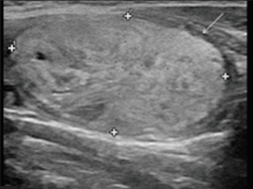

Nhân tuyến giáp là vùng mô trong tuyến giáp tăng sinh khu trú, có thể là nhân đặc, nang hoặc hỗn hợp, được phát hiện chủ yếu bằng siêu âm. Đa số nhân tuyến giáp lành tính; chẩn đoán xác định bản chất thường dựa trên kết hợp lâm sàng, siêu âm và chọc hút tế bào kim nhỏ (FNA) 2,3.

Hình 1: Hình minh hoạ nhân tuyến giáp